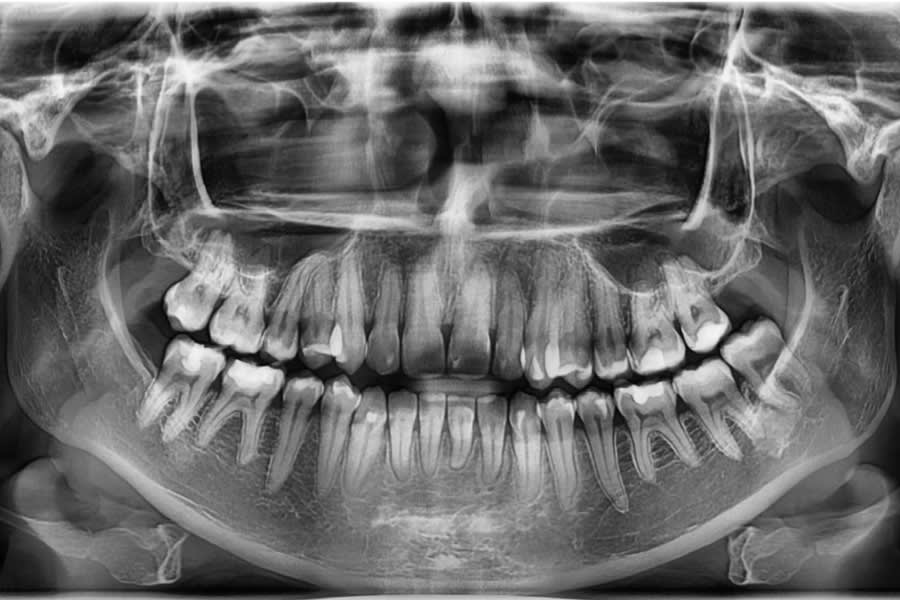

Radiographic Follow-up

Panoramic/cephalometric re-evaluation is used to document posterior intrusion without root resorption or sinus compromise, improved upper incisor angulation in bone, lip profile changes consistent with CCW autorotation, and favorable skeletal parameters.7,17-21 (Figure 18 through Figure 21)